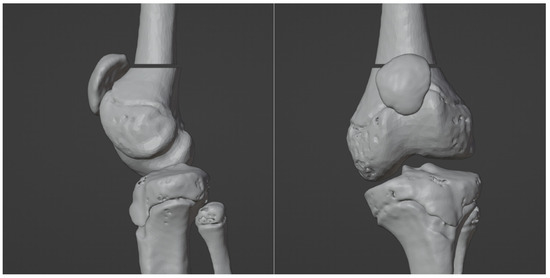

3.1. 3D Reconstruction of Patient-Specific CT Scan

3.4. Virtual Surgical Simulation